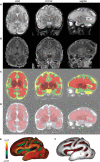

In the human brain, the morphology of cortical gyri and sulci is complex and variable among individuals, and it may reflect pathological functioning with specific abnormalities observed in certain developmental and neuropsychiatric disorders. Since cortical folding occurs early during brain development, these structural abnormalities might be present long before the appearance of functional symptoms. So far, the precise mechanisms responsible for such alteration in the convolution pattern during intra-uterine or post-natal development are still poorly understood. Here we compared anatomical and functional brain development in vivo among 45 premature newborns who experienced different intra-uterine environments: 22 normal singletons, 12 twins and 11 newborns with intrauterine growth restriction (IUGR). Using magnetic resonance imaging (MRI) and dedicated post-processing tools, we investigated early disturbances in cortical formation at birth, over the developmental period critical for the emergence of convolutions (26-36 weeks of gestational age), and defined early 'endophenotypes' of sulcal development. We demonstrated that twins have a delayed but harmonious maturation, with reduced surface and sulcation index compared to singletons, whereas the gyrification of IUGR newborns is discordant to the normal developmental trajectory, with a more pronounced reduction of surface in relation to the sulcation index compared to normal newborns. Furthermore, we showed that these structural measurements of the brain at birth are predictors of infants' outcome at term equivalent age, for MRI-based cerebral volumes and neurobehavioural development evaluated with the assessment of preterm infant's behaviour (APIB).